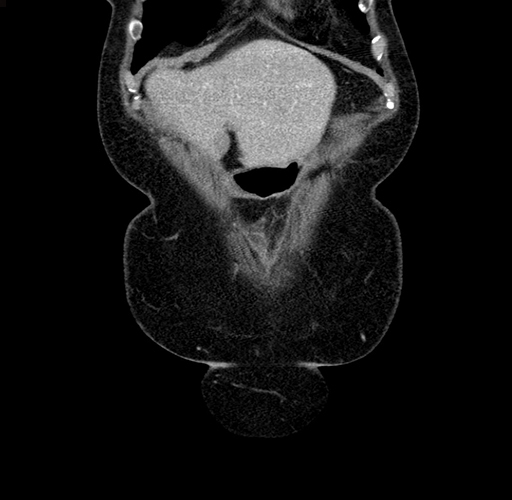

MRI T1